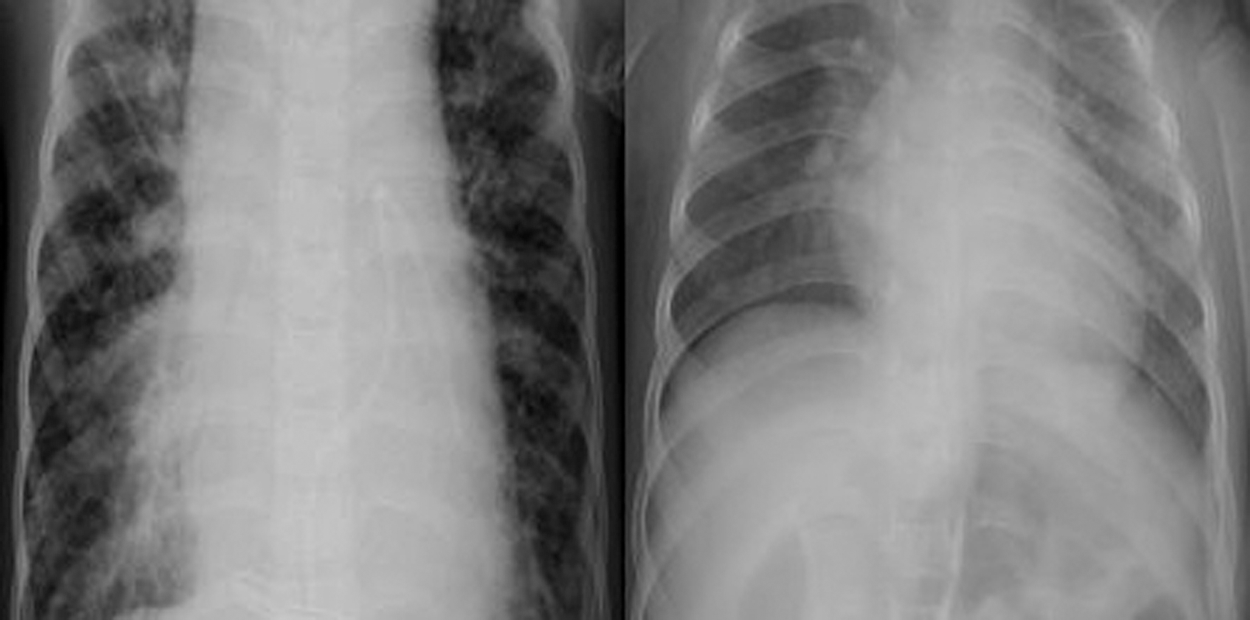

Figs. 1 and 2 show samples of normal and COVID-19 X-ray images, respectively.

Figure 1: Two normal X-ray images

Figure 2: Two COVID-19 X-ray images